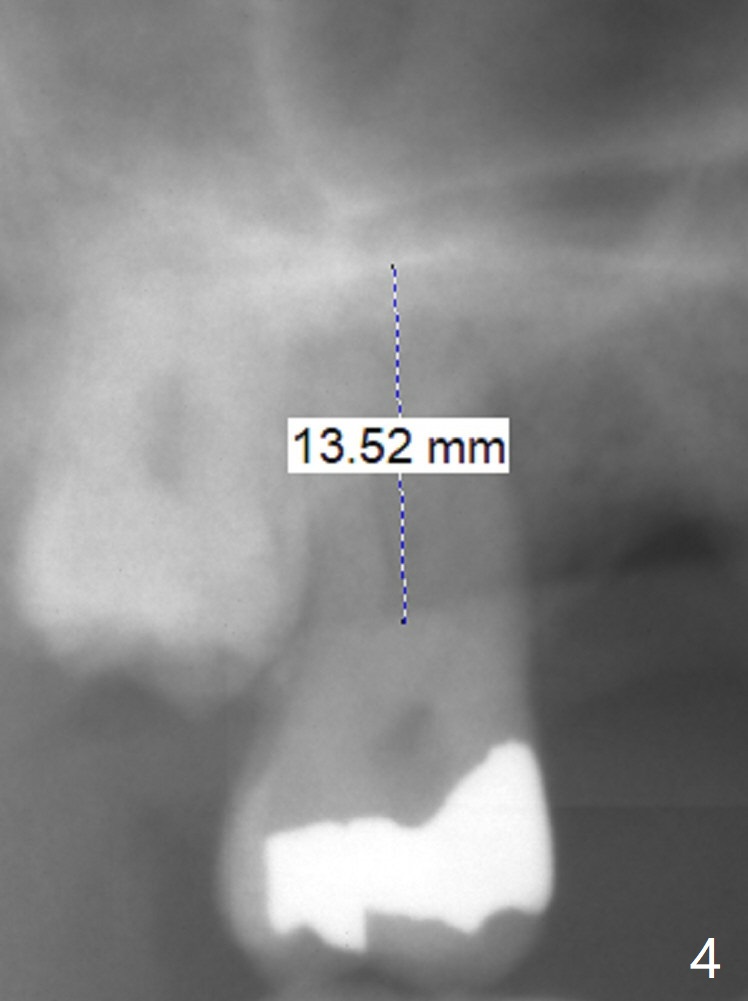

A 58-year-old man had 2 missing molar 3 years ago (Fig.1). Later the tooth #2 fractures with apparently severe bone loss (Fig.2). If the septum is lost, bone height is around 3 mm (Fig.3). Take PA before using Magic Sinus Lifter. Since his bone density is high, increase exposure time. If the septum is present (Fig.4), use Magic Drills sequentially (1.6, 2.8, 3.2 mm ....). PRF plug and membrane (1 each) are to be prepared.